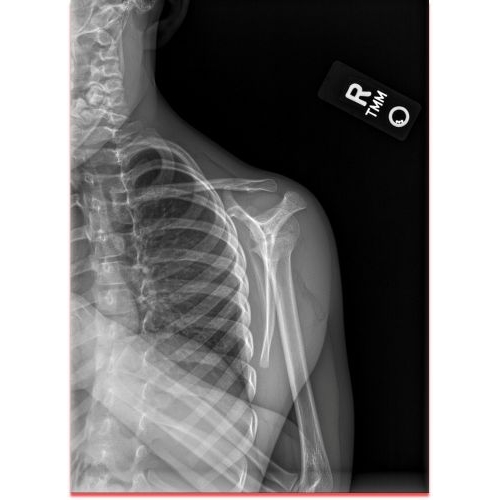

| Monkey Bar Mishap: A Unique Scapulothoracic Injury And Presentation - Page #3 | |||